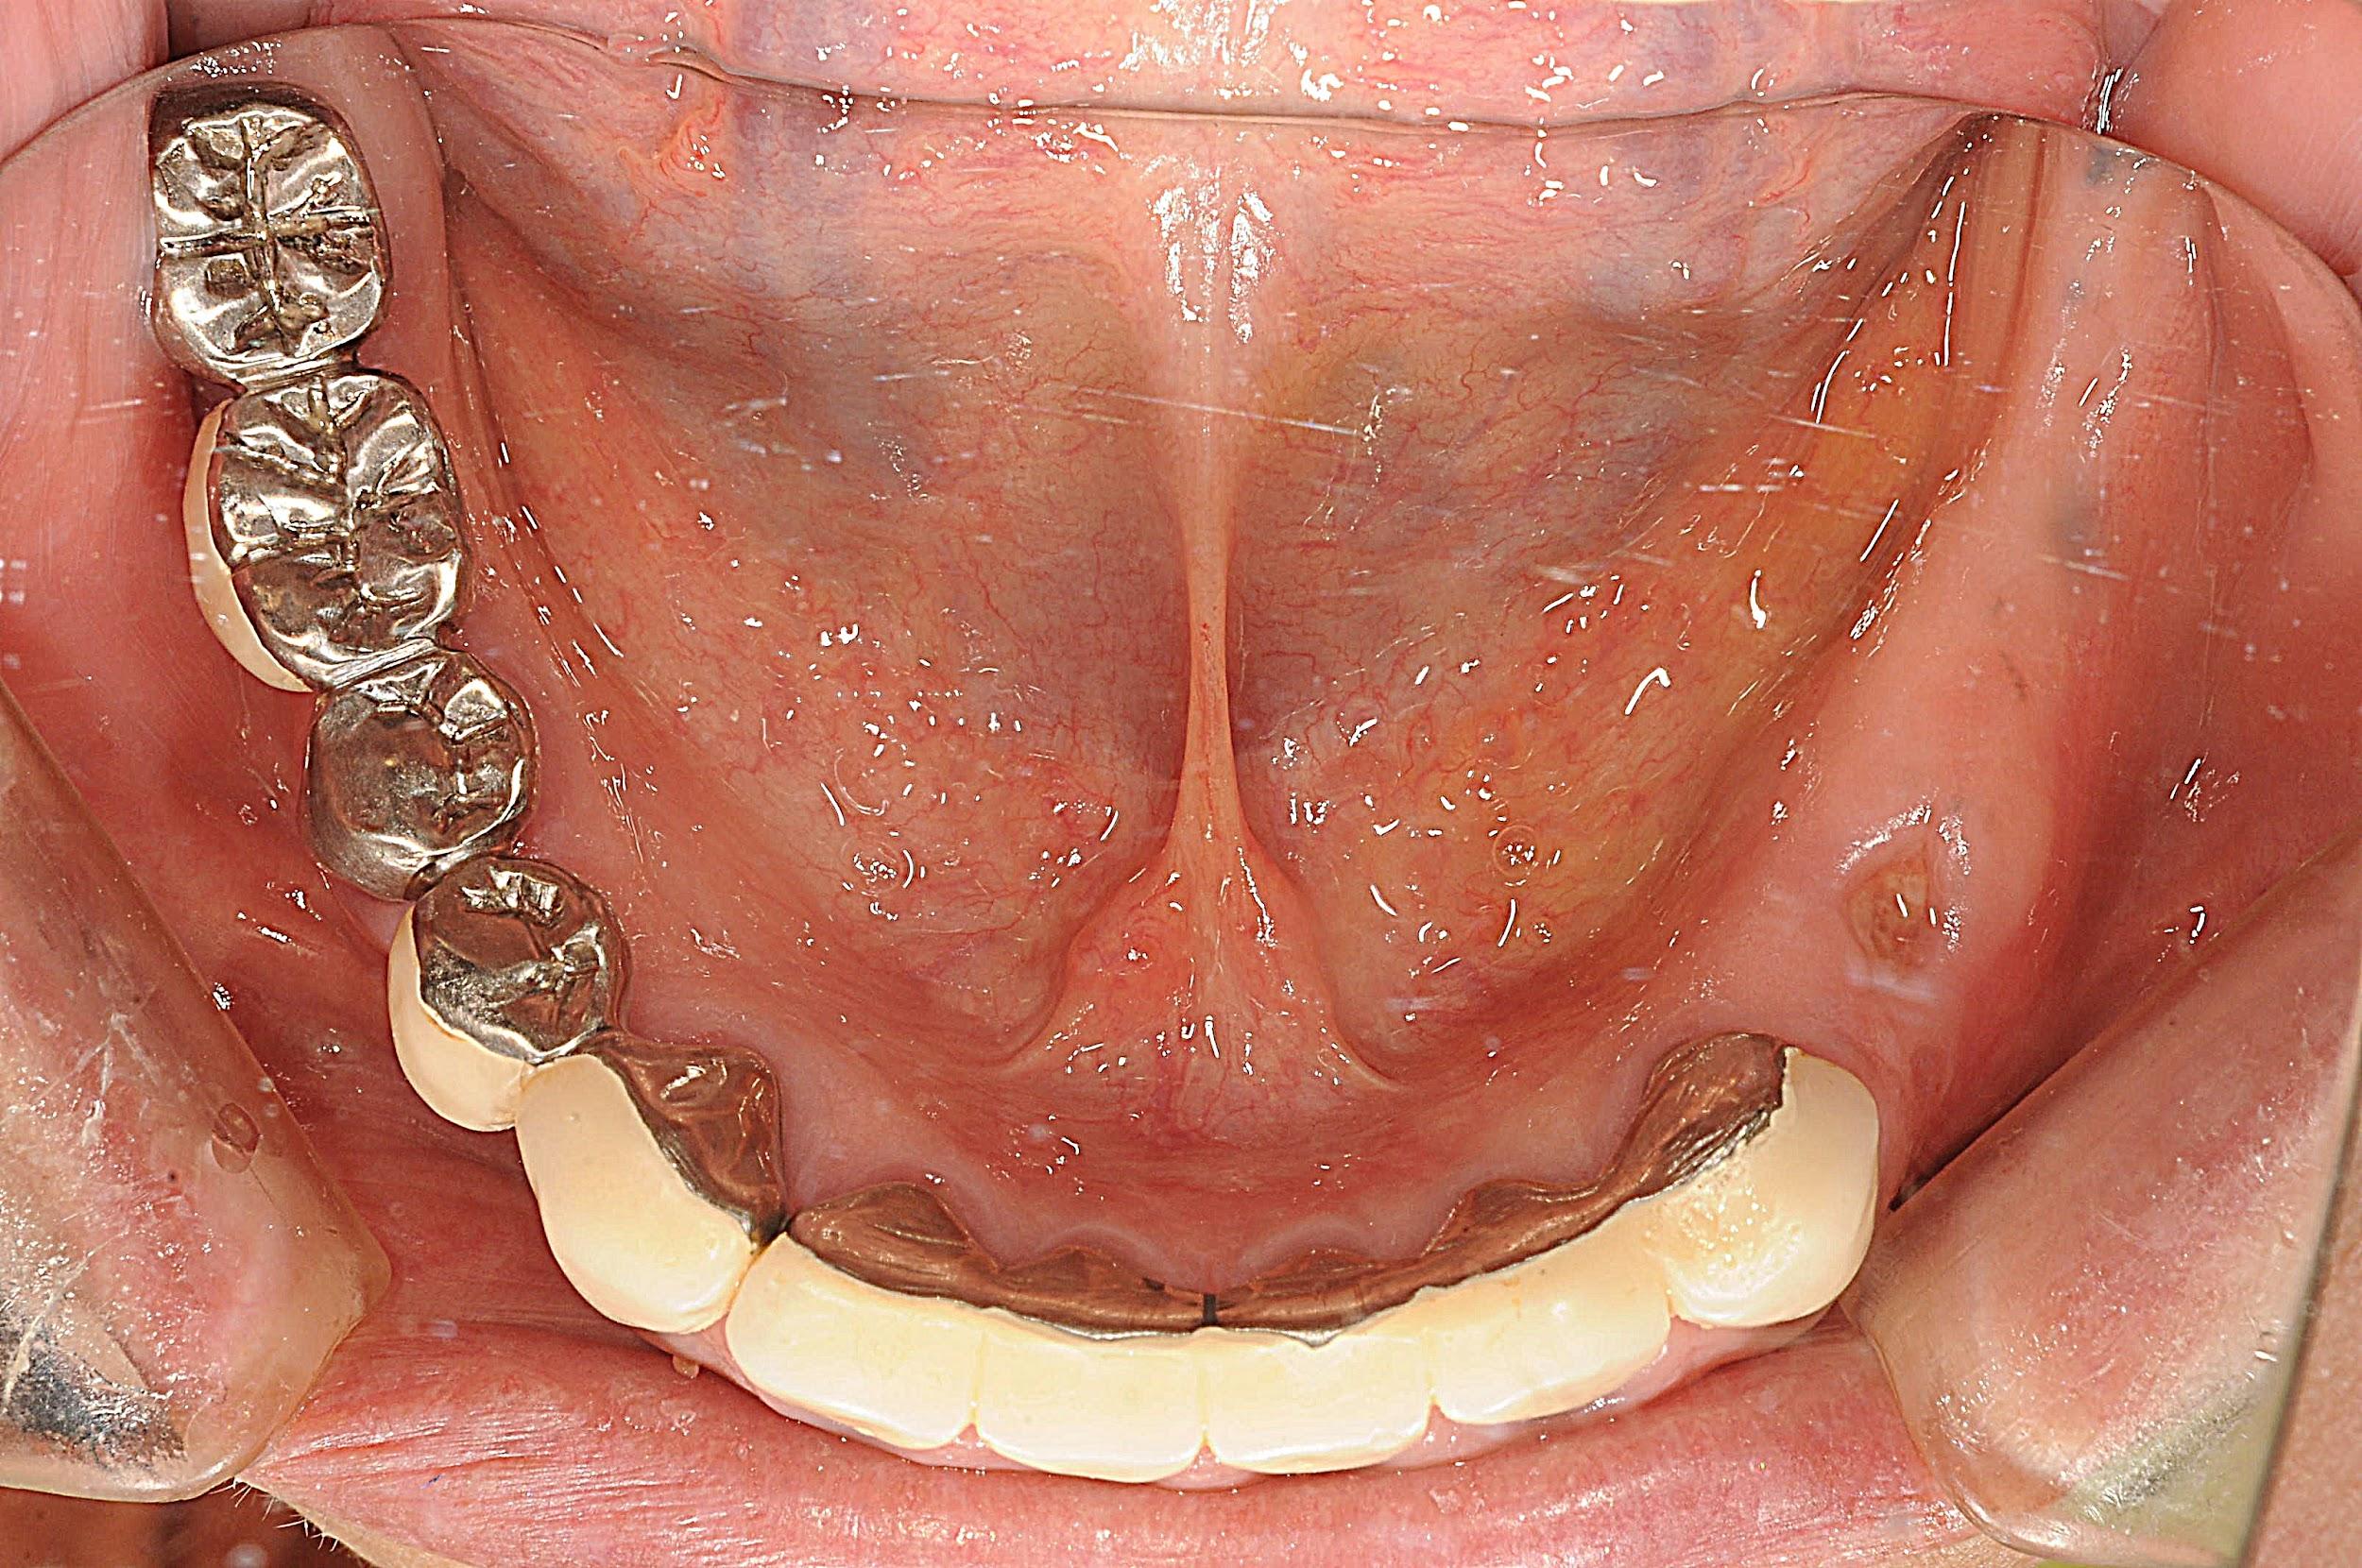

・広範な歯の欠損と歯周炎: すでに多くの歯を失っている箇所(欠損)に加え、残っている歯も中等度以上の歯周炎が認められました。 ・咬合(噛み合わせ)の崩壊: 歯を失ったまま放置されていた期間があったため、噛み合わせの支えが失われ、お口全体のバランスが大きく崩れている状態でした。

3. インプラント埋入(計7本)と骨造成

欠損部分へインプラントを配置。骨が不足している箇所には、骨を作る材料(骨造成)を使用し、強固な土台を作ります。

5. ジルコニア補綴による審美修復

前歯を含めた最終的な被せ物には、歯科用セラミックの中でも極めて強度と美しさを持つジルコニアを採用します。

・治療内容: インプラント埋入(7本)、ジルコニア補綴、骨造成(GBR) ・治療期間: 約1年9か月(術後の安定確認期間含む) ・費用: 約450万円(税込) ・リスク・副作用: インプラントは外科手術を伴うため、術後に一時的な腫れ、痛み、内出血が生じる場合があります。また、喫煙の再開や毎日のセルフケアの怠慢は「インプラント周囲炎」を招き、最悪の場合インプラントが脱落する可能性があります。長期的な安定には、プロによる定期的なメンテナンスが必須です。